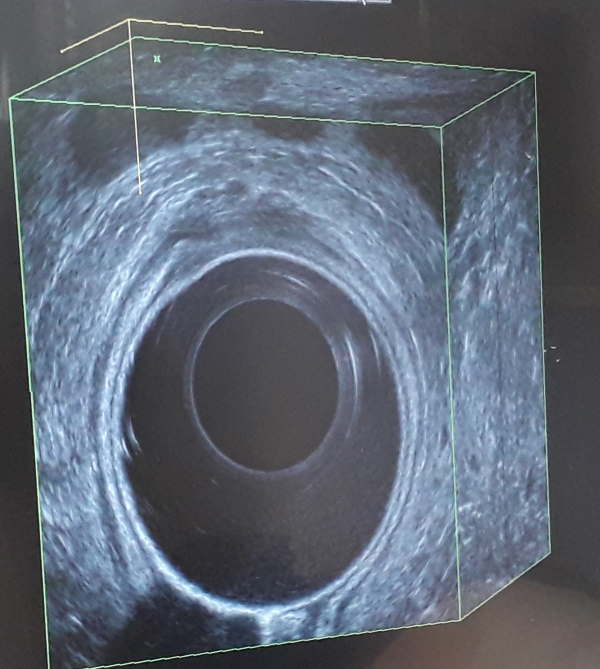

L'ecografia transrettale ha lo scopo di studiare l'ultimo tratto dell'intestino, un organo cilindrico e le immagini che vengono mostrate vedono un centro nero (la sonda) e la superficie circostante.

La sonda è detta a cristallo rotante, perchè l'impulso ecografico non è in una direzione ma è circolare tutto attorno alla sonda.

La sonda è del calibro di un dito e una volta posizionata resta ferma perchè dispone di pulsanti che consentono allo specialista di far scorrere il cristallo all'interno della sonda in modo da vedere tutti i piani dell'intestino.

La sonda è all'interno del retto e di conseguenza consente di produrre immagini, le quali mostrano le strutture che compongono fisiologicamente l'organo, la mucosa, i muscoli, i vasi, i linfonodi e se i rapporti fisiologici sono rispettati. In presenza di situazioni patologiche viene evidenziata la presenza di masse o cavità e quindi se i rapporti fra i tessuti presenti sono variati.

L'immagine piana consente di vedere la presenza di una lesione come in una foto, perchè mostra dei piani trasversali alla lunghezza del retto.

L'immagine in 3D consente ulteriori osservazioni.

L'ecografo può raccogliere tutte le immagini e ricreare una ricostruzione in 3D che attraverso il touch screen consente di muoversi anche secondo il piano longitudinale e frontale. Il 3D consente di vedere la lunghezza di una lesione o lo spessore dei muscoli del retto.